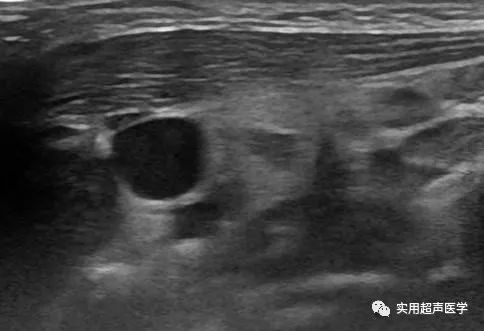

患儿,男,15天,发现左侧颈部肿块就诊。超声检查如下:

左侧胸锁乳突肌横切面

左侧胸锁乳突肌明显增粗,内探及异常回声结构,形态规则,边界可见,内为欠均质低回声混杂条状强回声交织成团,CDFI 于病变内可探及丰富血流信号显示。超声诊断为左侧胸锁乳突肌实质性病变,血供丰富。